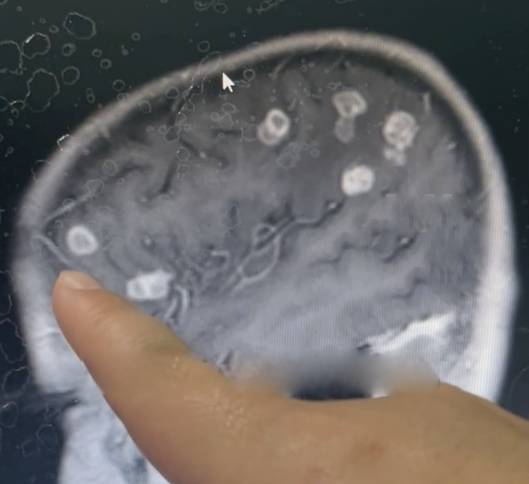

Kết quả kiểm tra khiến các bác sĩ vô cùng sốc khi não của bé bị nấm tấn công, xuất hiện hơn 20 lỗ rỗng có kích thước khác nhau, đe dọa tính mạng.

Các bác sĩ cho biết, khi bào tử nấm xâm nhập qua đường hô hấp, chúng có thể đi vào máu và tấn công mô não, gây tổn thương nghiêm trọng nếu không được điều trị kịp thời. Kết quả chụp MRI cho thấy não bé bị "gặm nhấm", tạo thành hơn 20 lỗ rỗng.

"Có khoảng 20 lỗ trên hình ảnh! Điều này rất hiếm gặp", bác sĩ giải thích.